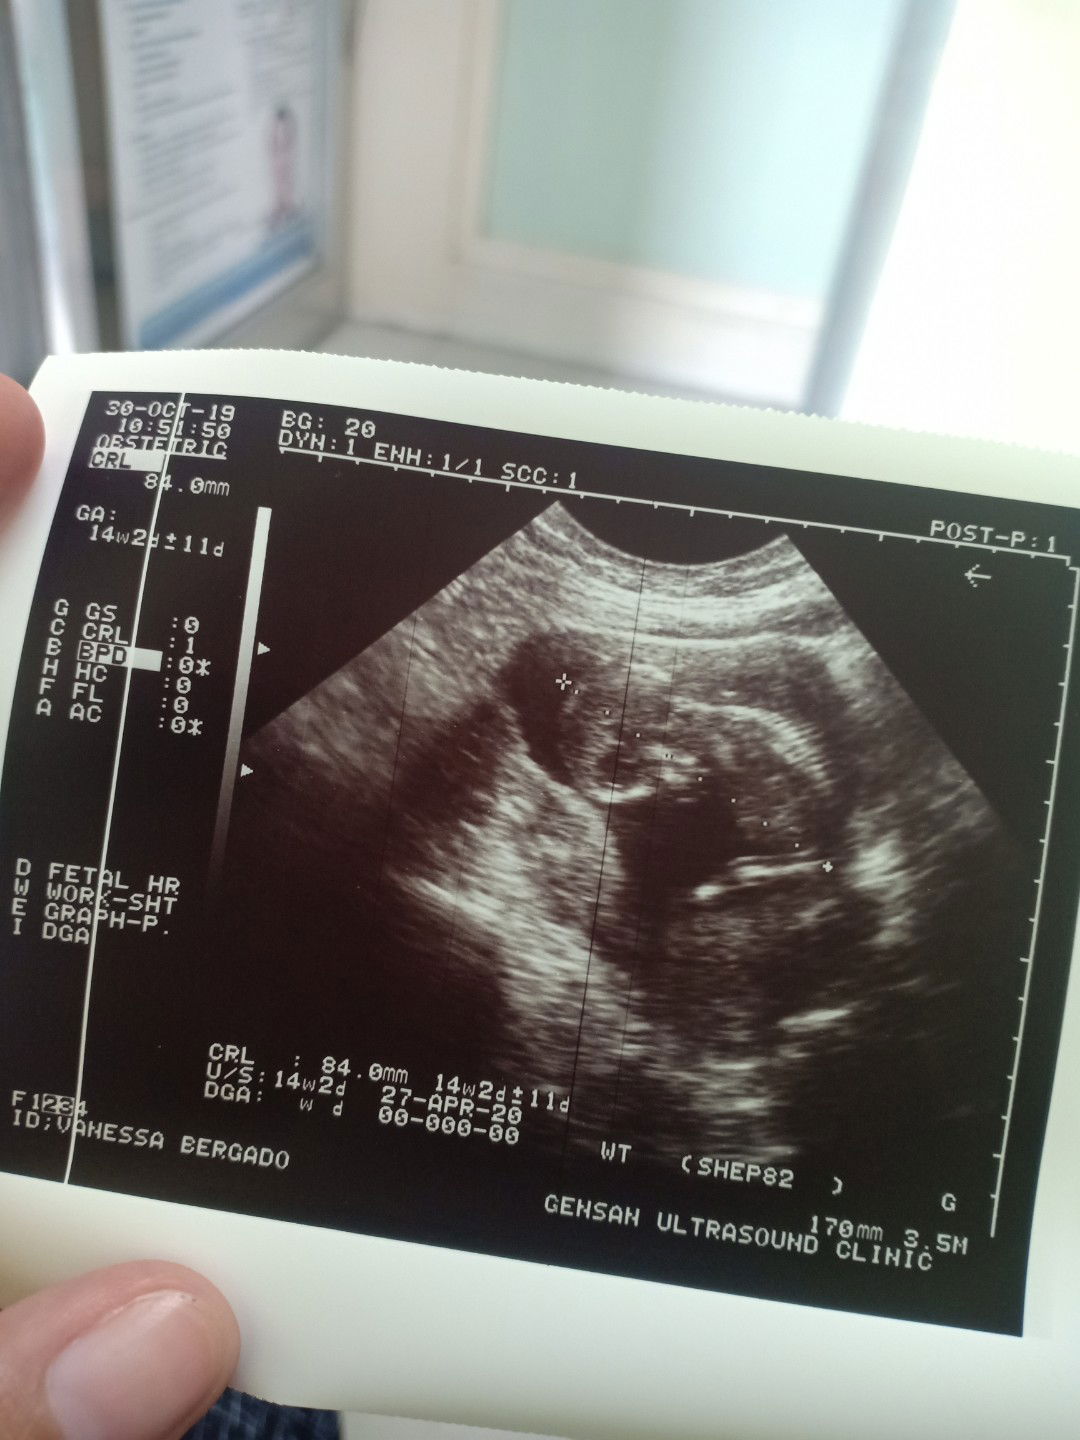

14th week contraction

Hello po. Nag pa check up ako kahapon dahil ilang araw sumasakit tiyan ko. Nakita sa ultrasound na nag contract daw uterus ko kaya naiipit si baby sa loob. Sabi ng OB possible na stress ang dahilan. Niresetahan nya ko ng tocolytic na gamot. Ano pa po kaya pwede kong gawin? Na experience nyo rin ba to? Natatakot kasi ko, 1st baby namin to. ?